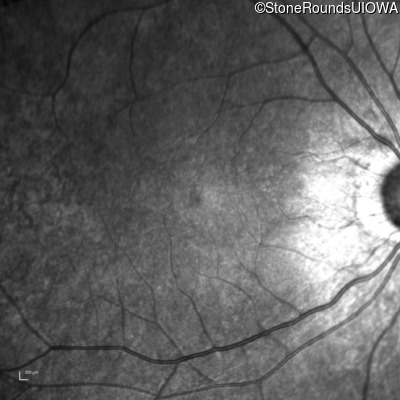

Infrared Fundus Photograph - Right - 20/25 -3

Exemplar